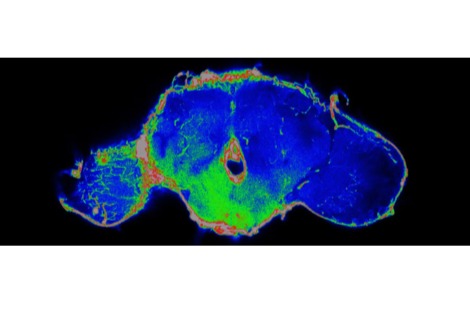

ثم استُخدمت هذه الخلايا المُعدّلة لزراعة أنسجة جلدية، زُرعت على فئران. بعد التئام الطعوم واندماجها مع الأنسجة المحيطة، تصرفت البشرة المُهندسة بشكل مشابه للبشرة الطبيعية، باستثناء فرق جوهري واحد. فعندما يحدث التهاب داخل الجسم، تبدأ المنطقة المزروعة بالتوهج باللون الأخضر.

يُترجم هذا التوهج إشارة جزيئية غير مرئية إلى إشارة مرئية، مما يسمح بقراءة النشاط البيولوجي الداخلي مباشرةً على سطح الجلد. ولأن المستشعر مصنوع من خلايا جذعية حية، فهو لا يعتمد على الإلكترونيات أو مصادر الطاقة أو الاستبدال الدوري. ومع تجدد الجلد بشكل طبيعي، تستمر الخلايا الجذعية المُهندسة في إنتاج خلايا استشعار جديدة.

وقال شوجي تاكيوتشي من جامعة طوكيو في بيان صحفي: "على عكس الأجهزة التقليدية التي تتطلب مصادر طاقة أو استبدالًا دوريًا، يُحافظ الجسم نفسه على هذا النظام بيولوجيًا. في تجاربنا، استمرت وظيفة المستشعر لأكثر من 200 يوم، حيث جددت الخلايا الجذعية المُهندسة البشرة باستمرار."